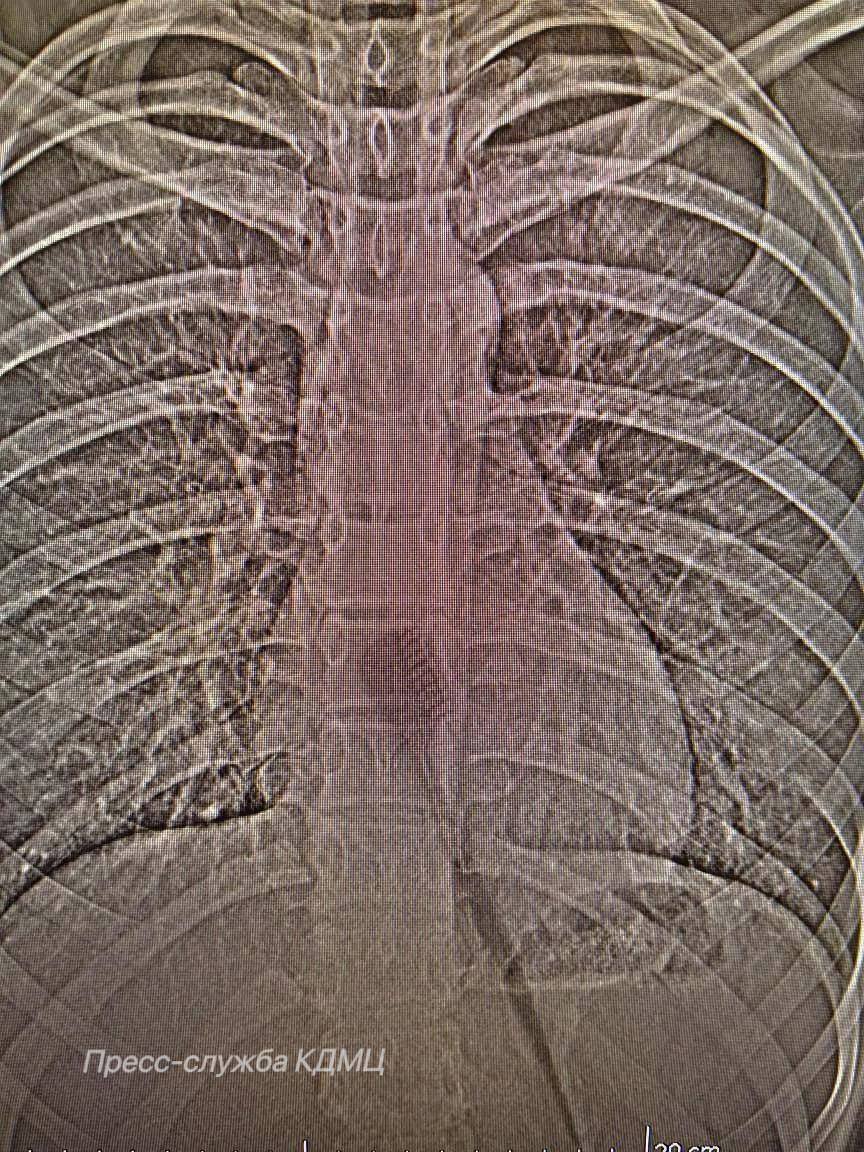

Об уникальном медицинском случае рассказали в Горздраве Челнов. На приём доставили 13-летнюю девочку, которая во время утренней гигиены случайно проглотила зубную щетку длиной 19 сантиметров. Инородный предмет находился в желудке и частично в пищеводе, создавая угрозу внутренних повреждений.

Пациентке провели эндоскопическую операцию. Этот малоинвазивный метод позволяет удалять инородные предметы без разрезов, через естественные пути.